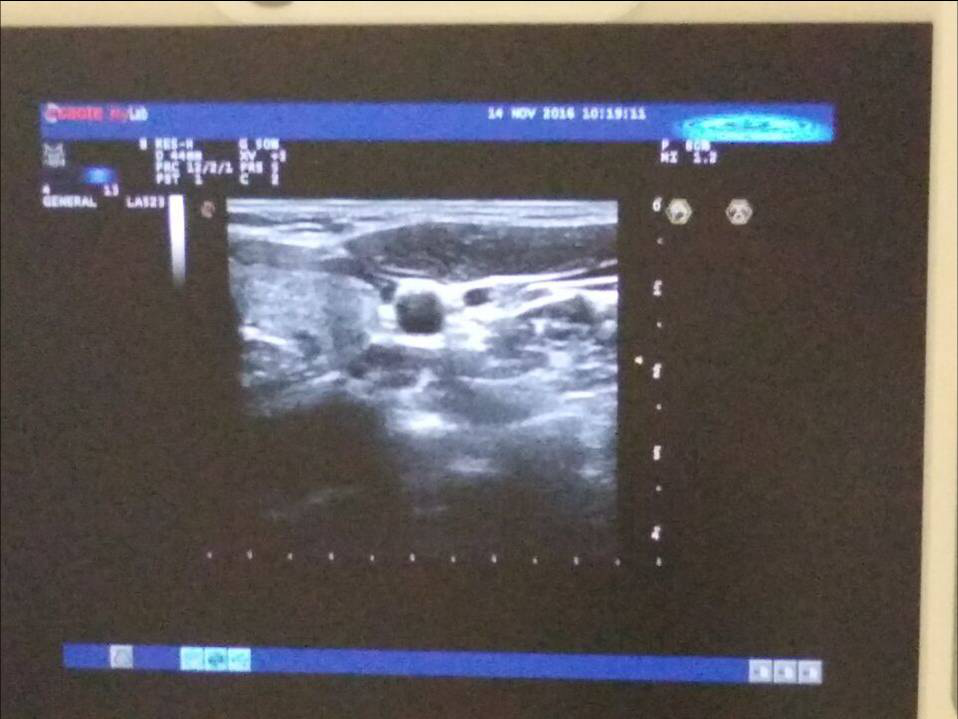

穿刺過程中,彩超顯示圖片